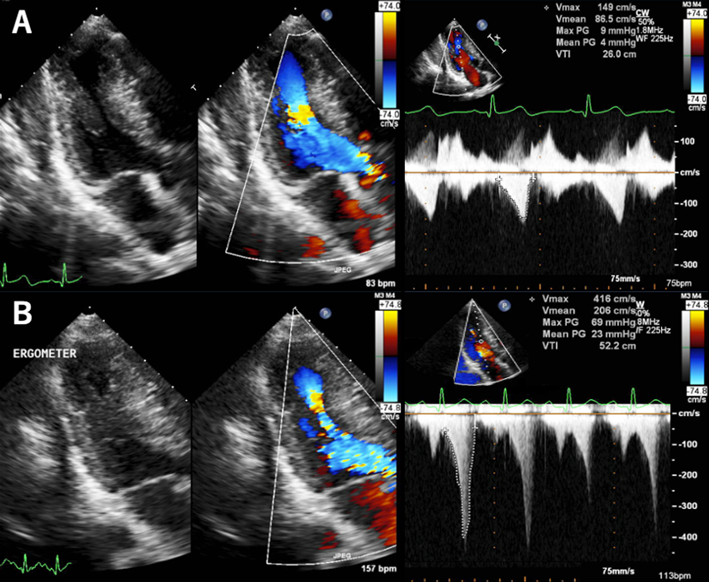

運動負荷心エコー図により心室中部閉塞を診断することができた無症候性小児肥大型心筋症の1例Asymptomatic Pediatric Hypertrophic Cardiomyopathy Diagnosed as Midventricular Obstruction by Exercise Stress Echocardiography